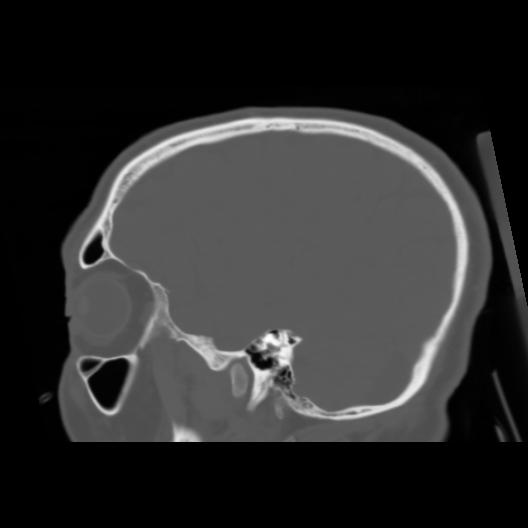

6 CEREBRO,,Sagittal,3.000,CEREBRO,Sagittal,